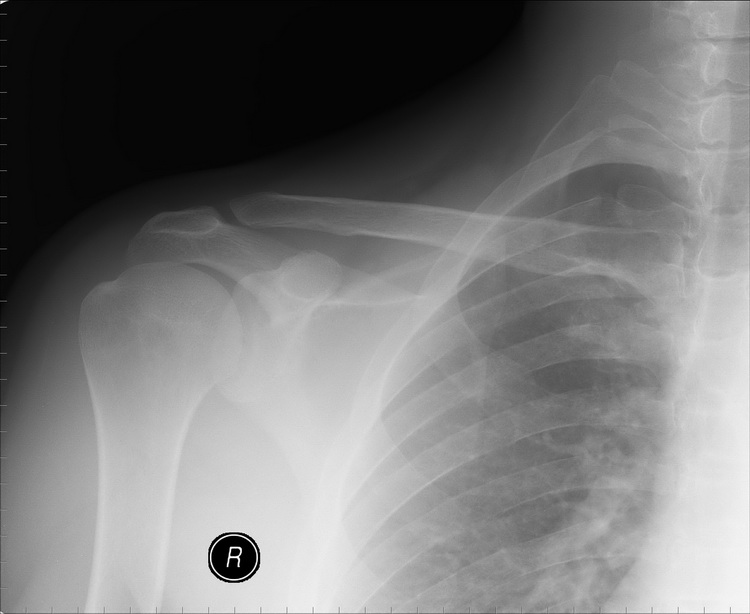

Re: Остеолиз ключицы

Еще снимки.